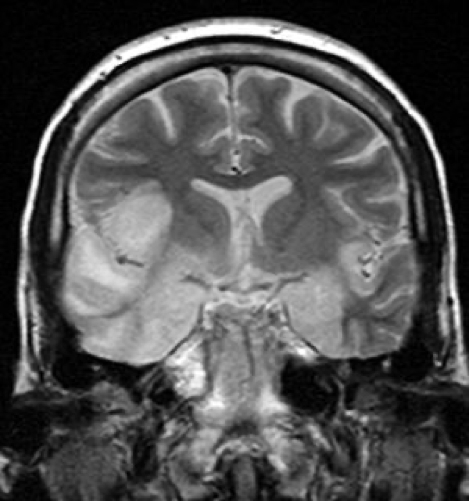

MRI Brain

- High signal intensity in the temporal lobes and inferior frontal gyrus (classic for HSV encephalitis)